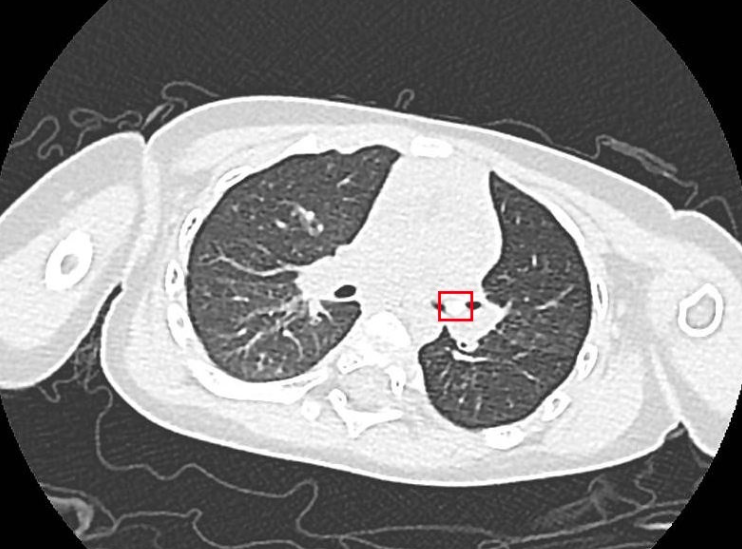

结果出来了,医生发现在小希的左侧支气管内有一个直径仅为4毫米的异物。小希妈妈想起半个多月前给她喂过一颗葡萄。儿科医生团队讨论后,推测当时小希可能发生过呛咳,异物很可能是一粒葡萄籽!

随后,通过电子纤维支气管镜,医生在小希的支气管中精准找到了异物,用特制的异物钳小心翼翼地夹住后慢慢取出来,果然是一粒葡萄籽。取出异物后,小希咳嗽喘息的症状明显减轻,吃奶和睡觉很快正常了。

医生从宝宝的支气管中取出了一粒葡萄籽。